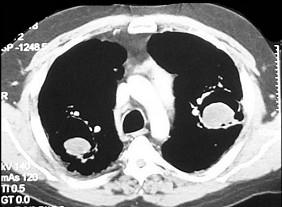

问题 男,48岁,发热,咳嗽,咳痰,咯血,PPD(-),请结合图,最可能的诊断是 ( )

选项 A.肺癌 B.肺曲菌病 C.肺结核 D.肺炎 E.肺脓肿

答案 B